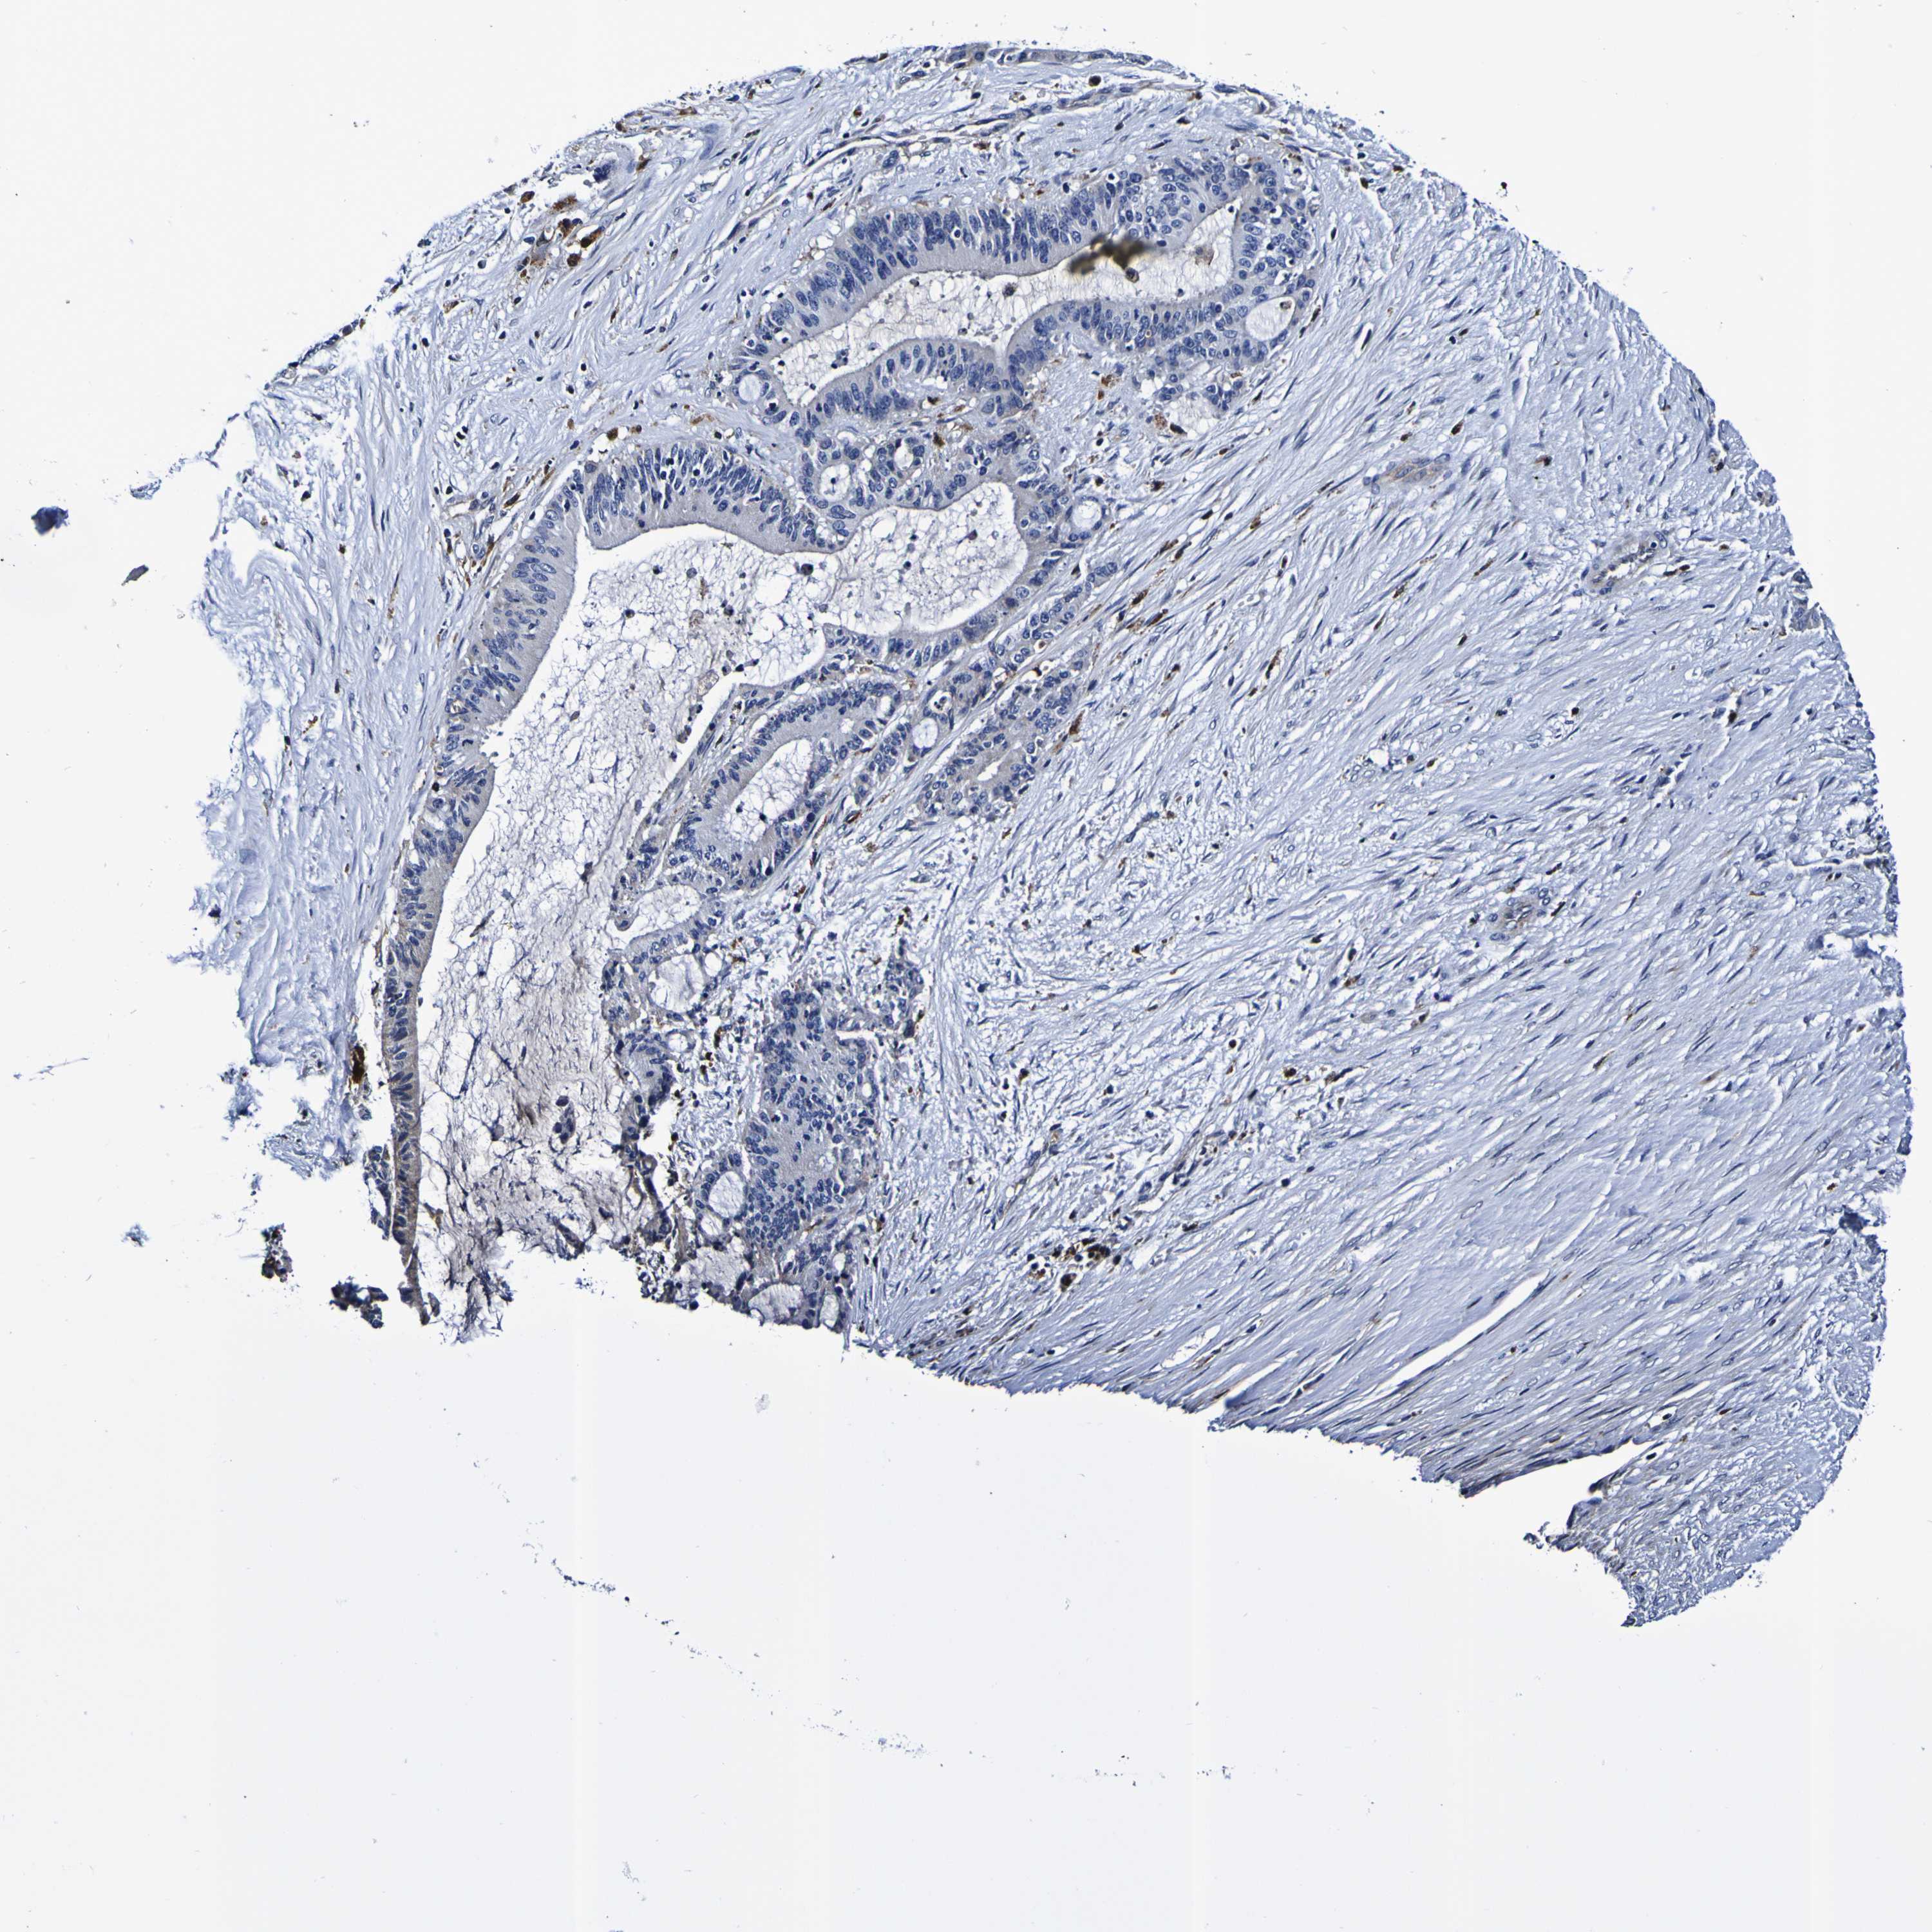

LIVER CANCER - Protein expressioni

A mouse-over function shows sample information and annotation data. Click on an image to view it in a full screen mode. Samples can be filtered based on level of antibody staining by selecting one or several of the following categories: high, medium, low and not detected. The assay and annotation is described here.

Note that samples used for immunohistochemistry by the Human Protein Atlas do not correspond to samples in the TCGA dataset.

Antibody stainingi

Antibody staining in the annotated cell types in the current human tissue is reported as not detected, low, medium, or high, based on conventional immunohistochemistry profiling in selected tissues. This score is based on the combination of the staining intensity and fraction of stained cells.

Each image is clickable and will lead to virtual microscopy that enables deeper exploration of all samples and also displays staining intensity scores, fraction scores and subcellular localization as well as patient and tissue information for each sample.

Antibody HPA044758

Antibody CAB011582

Cholangiocarcinoma

Carcinoma, Hepatocellular, NOS